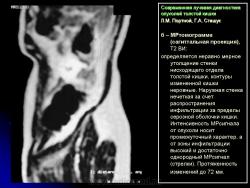

Протокол исследования включал применение импульсных последовательностей (ИП): SE в режиме Т1 с компенсацией дыхания, FSE, STIR (Т2 с синхронизацией дыхания). Основными МРсимптомами опухолевого поражения стенки кишки являются: неравномерное ее утолщение на ограниченном протяжении с соответствующим сужением просвета кишки, наличие внутрипросветного образования с неровными очертаниями и из менением МРсигнала (рис. 14). Толщина пораженной стенки кишки составляла от 7 до 40 мм. Очертания внутренних контуров стенки на уровне поражения были не ровные, бугристые. Интенсивность МРсигнала от из мененной стенки как на Т1, так и на Т2 ВИ была промежуточной (рис. 15), однородность сигнала зависела от преобладания процессов, развивающихся в опухолевой ткани: при имеющихся зонах распада на Т2 ВИ выявлялись очаги повышенной интенсивности МРсигнала. При использовании программы STIR интенсивность сигнала от опухолевой ткани была высокой. Распространение опухолевой инфильтрации за пределы стенки кишки характеризовалось нечеткостью наружных границ опухоли, сетчатым рисунком клетчатки с гетерогенным изменением Мрсигнала, более выраженным на Т1 ВИ (рис. 16б). При прорастании опухоли в смежные органы и структуры не визуализировались границы между измененной стенкой кишки и органом, на который распространялась опухолевая инфильтрация (рис. 17).